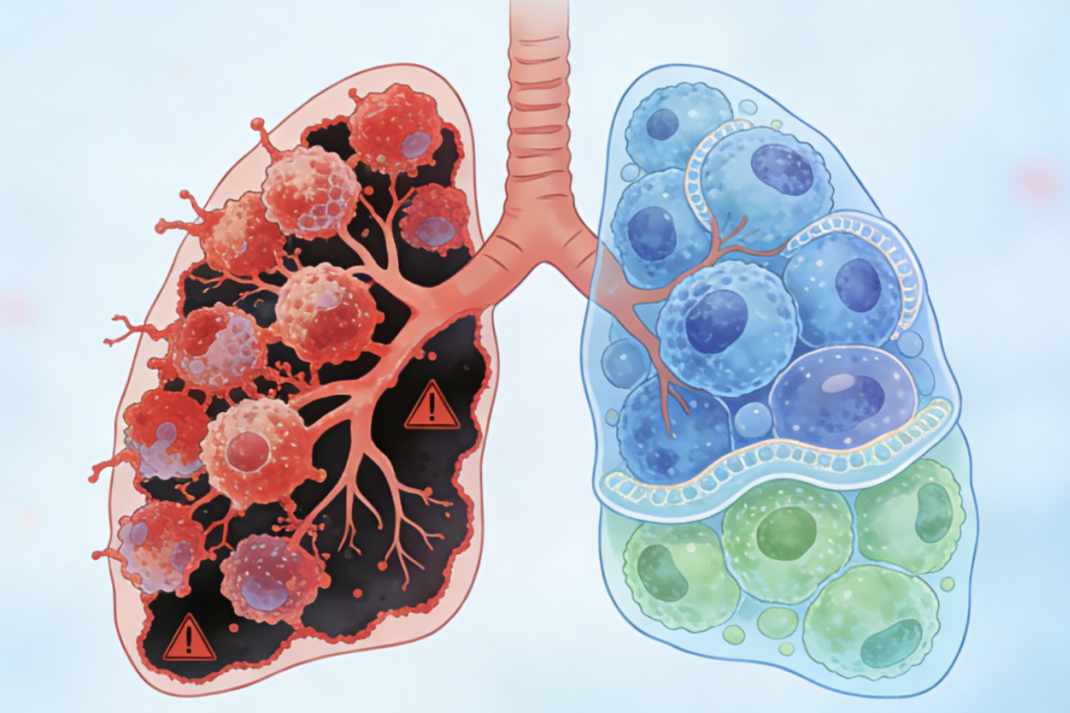

很多人提到肺癌,第一反应就是咳嗽、咳痰,甚至觉得不咳嗽就和肺癌无关。这种认知其实很片面,肺癌作为一种全身性疾病,早期症状常常不典型...[详情]

作为我国第一大高发癌种,每天都能遇到面对肺癌晚期进退两难的患者和家属:治,怕人财两空、痛苦加剧;不治,又于心不忍、满是遗憾。 但...[详情]

TAG标签:中医抗癌 肺癌